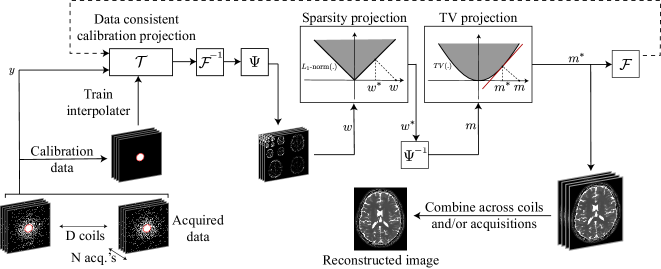

Refer to caption

Figure 1: Flowchart of the PESCaT reconstruction. PESCaT employs an alternating projections onto sets approach with three subprojections: data-consistent calibration projection, sparsity projection, and TV projection. The calibration projection linearly synthesizes unacquired k-space samples via a tensor interpolating kernel. The sparsity projection jointly projects wavelet coefficients of the multi-coil, multi-acquisition images onto the epigraph set of the 1subscript1\ell_{1}-norm function. The TV projection projects image coefficients onto the epigraph set of the TV-norm function. These projections are performed iteratively until convergence. Lastly, reconstructed images are combined across multiple coils and/or acquisitions.

where ϵ1,lssubscriptitalic-ϵsubscript1𝑙𝑠\epsilon_{\ell_{1},ls} are the constraints on the sparsity of the reconstruction, and ϵTV,ndsubscriptitalic-ϵ𝑇𝑉𝑛𝑑\epsilon_{TV,nd} are the constraints on the TV of the reconstruction. The optimization problem in (5) was solved via an alternating projections onto sets algorithm. As outlined in Fig. 1, this algorithm involves three consecutive projections, namely data-consistent calibration, sparsity, and TV projections. The calibration projection linearly synthesized unacquired k-space samples via the tensor interpolating kernel. To perform this projection while enforcing strict consistency to acquired data, an iterative least-squares algorithm was employed [28]. The sparsity projection jointly projected wavelet coefficients of images onto the epigraph set of the 1subscript1\ell_{1}-norm function. The TV projection projected image coefficients onto the epigraph set of the TV-norm function. These projections were performed iteratively until convergence. At each iteration, MSE between the reconstructed image in the current iterate and the previous iterate was first measured, and the percentage change in MSE across consecutive iterations was then calculated. Convergence was taken to be the iteration at which the percentage change in MSE fell below 20%. Lastly, reconstructed images were combined across multiple coils and/or acquisitions. Note that because PESCaT is structured modularly regarding the calibration, sparsity, and TV projections, it is trivial to implement variants that only employ sparsity or TV regularization.